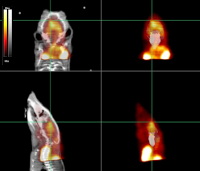

Entry-level preclinical PET scanner for small animal imaging research and training of medical imaging technologists.

Upgraded systems specially designed and engineered for advanced preclinical imaging research (iPET) and organ-dedicated PET.